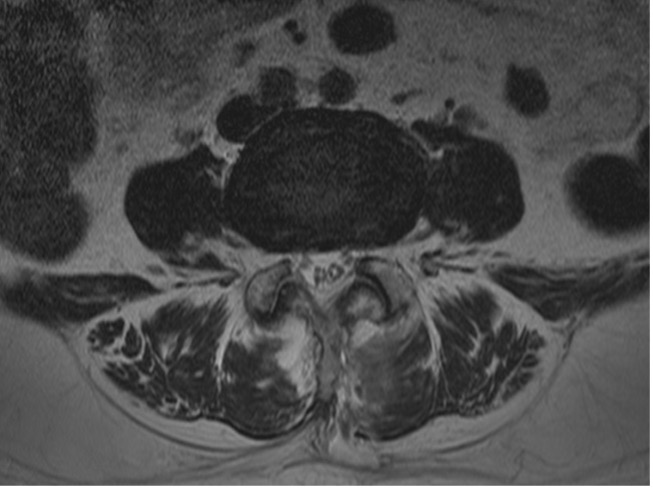

척추관협착증

척추관협착증이란

어떤 원인으로 척추 중앙의 척추관, 신경근관 또는 추간공이 좁아져 허리의 통증의 유발하거나 다리에 여러 복합적인 신경증세를 일으키는 질환

입니다.

디스크를 구성하는 수핵과 섬유륜에 퇴행성 변화가 일어나고 척추관을 구성하는 뼈와 인대 등이 두꺼워져 척추 뼈가 어긋나는 경우 척추 신경을 눌러 통증을 일으킵니다.